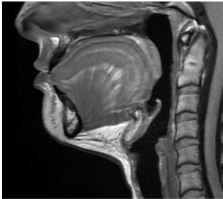

Before

After

Before

After